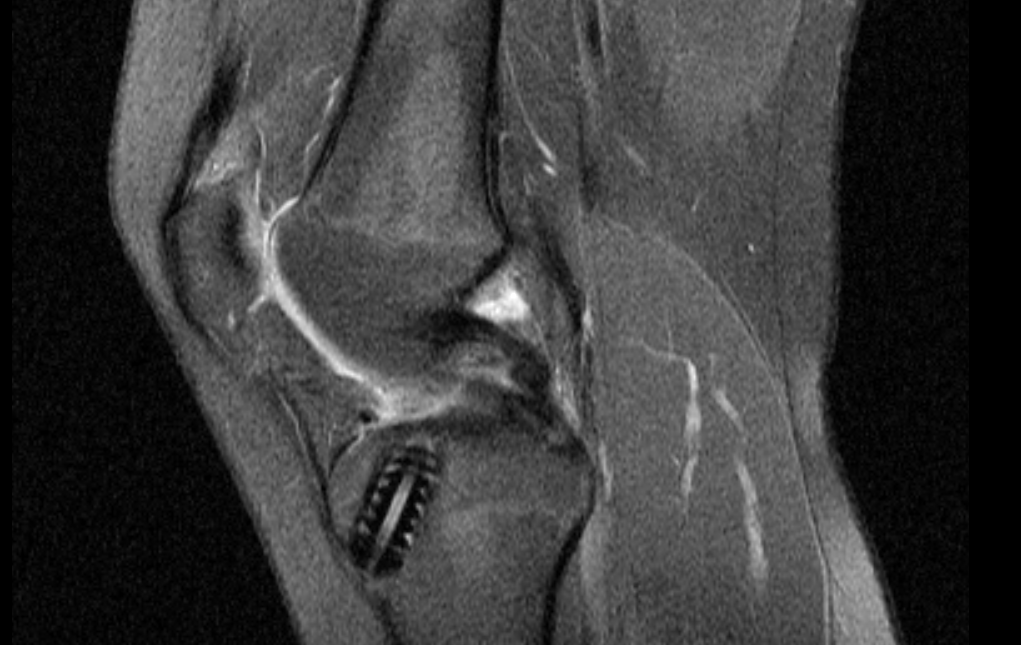

Kann mir jemand bei der Auswertung von MRT Bildern am Knie geben? (Arzt, Bluterguss, Radiologie)

MRT Befund rechtes Knie ist da irgendwie ne OP notwendig?

Meniskus gerissen MRT? (Knie, MRT Befund, Radiologie)

MRT Knie, weiße Schatten + Meniskusriss? (Schmerzen, Befund, Kniegelenk)